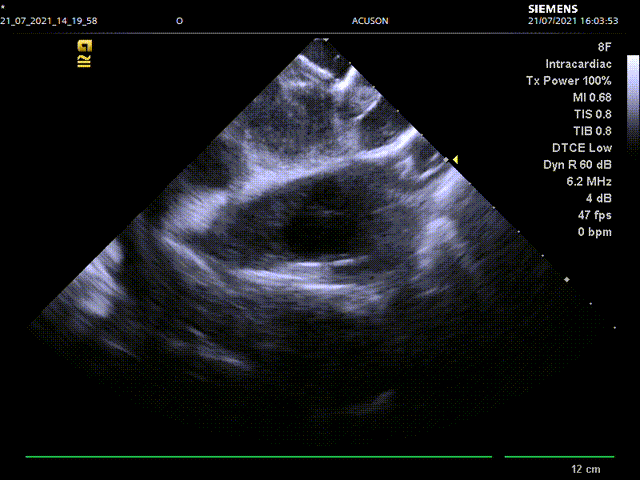

手术主要流程:经右股静脉入路,通过房间隔穿刺,将8F ICE导管送入左心房,在左心房通过三个不同的位置和角度测量左心耳锚定区大小和深度:左上肺静脉脊部角度、右肺静脉角度,二尖瓣环角度。而后进行左心耳造影,多种方式测量左心耳大小,选择合适病人情况的封堵器。放置左心耳封堵器后再用同样位置角度评估封堵情况。

经测量,选用LAmbre 2638型号封堵器,在ICE指导下进行封堵,再进行左上肺静脉脊部、右肺静脉,二尖瓣环三个角度的封堵情况评估和牵拉测试,最终释放封堵器。

心腔内超声评估封堵器牵拉试验

心腔内超声评估封堵器释放之后封堵情况